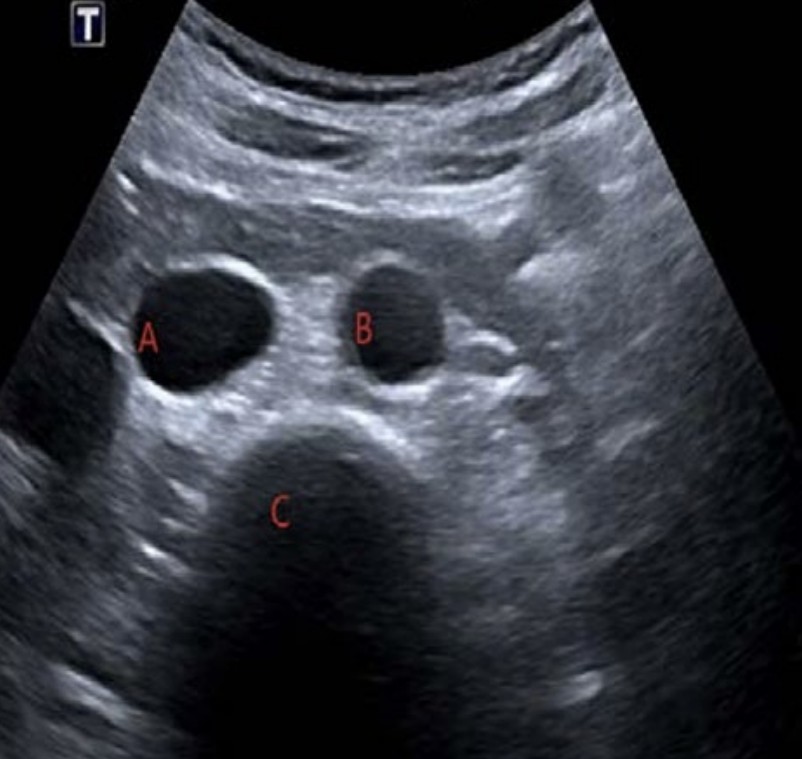

Presumed renal colic

A 75-year-old man is referred by his GP for presumed renal colic. He has worsening flank pain and is now …

2024 Term 2 Wk 9 Archived